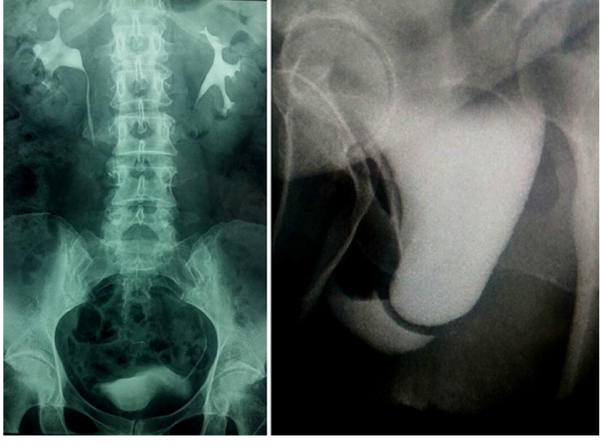

The physical examination demonstrated a full bladder that was palpable with complete closure of the introitus; the patient had a total fusion of the labia that did not allow the urethral meatus to be visible (Fig. 1).

An intravenous excretory pyelography was performed because it was impossible to place a Foley catheter for a retrograde cystography because the urethral meatus was impossible to locate or visualize. A progressive bladder prolapse was associated with the extrinsic compression of the abdomen, without any urine leakage, and during the voiding phase, the vagina was filled with urine, associated with an incomplete bladder emptying and vaginal collection of the voided urine (Fig. 2).